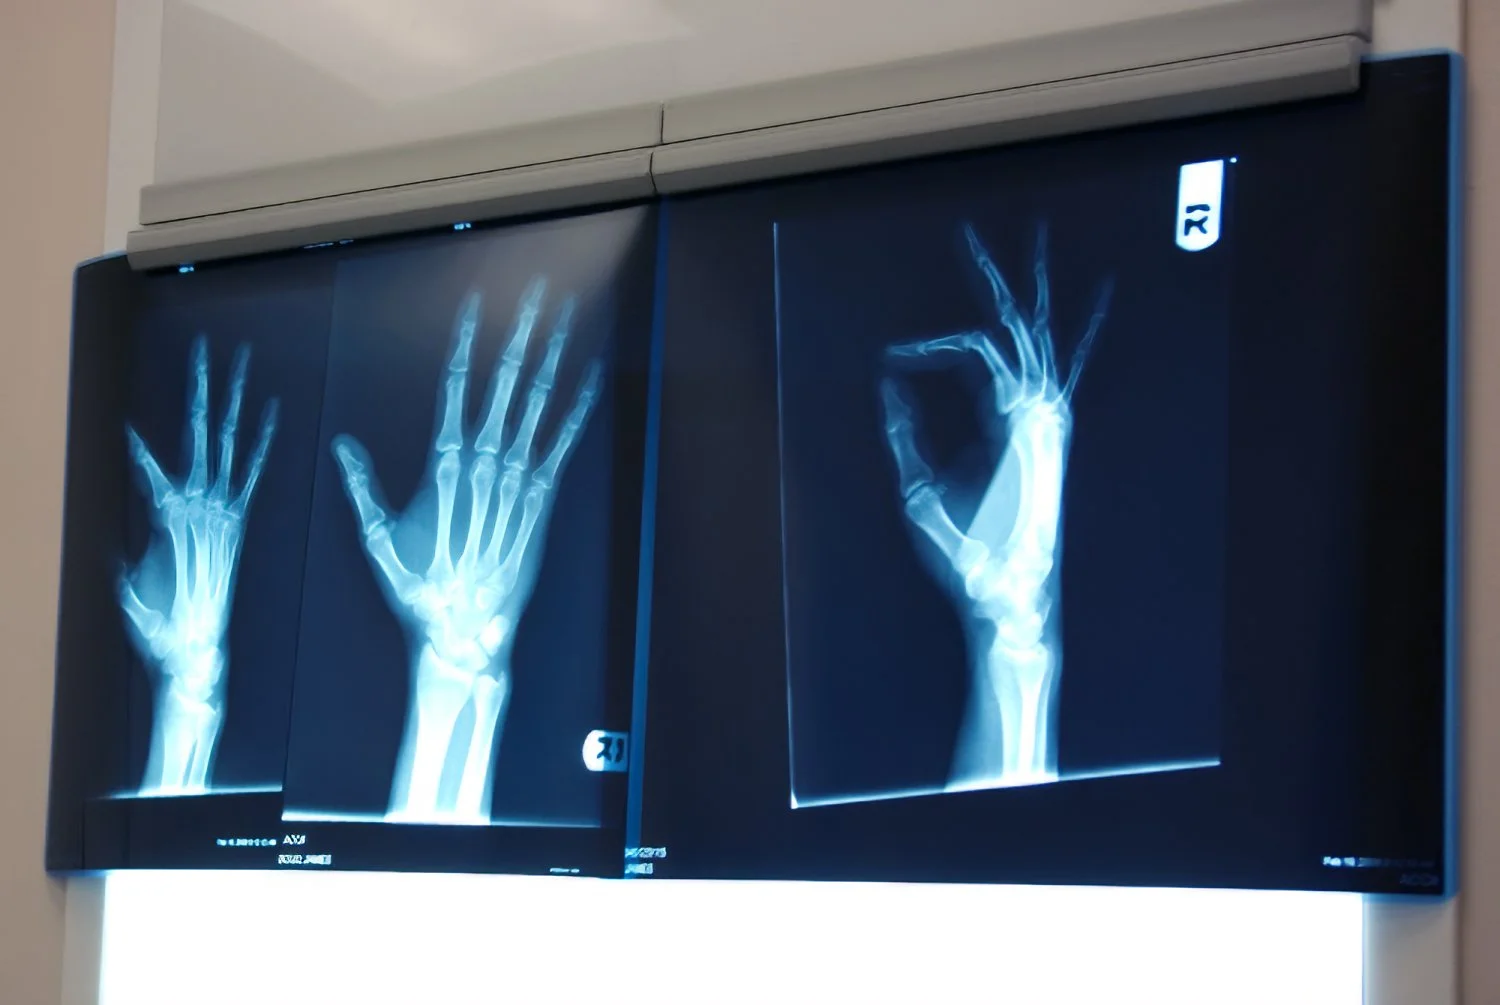

The nurse slid my X-rays under the clips of a wall-mounted light box, flipped the switch, and told me the doctor would be right in. I studied the X-rays while I waited, comparing my flesh and blood hand to the glowing photos. Huh, what's that squiggle running up my arm? A blood vessel? That's weird.

"Your bones look great," said the doctor. "But—" and then he looked over the questionnaire I'd filled out in the waiting room. "Ah, yes, diabetes. See this here?" he said, pointing to the light gray line running up the X-ray. "That's a blood vessel. It's not normal to see a blood vessel in an X-ray."

"Yeah, I was wondering about that."

"Yours are calcified. It's not uncommon to see it in someone who's had diabetes for as long as you have." He glanced at my questionnaire again and then went on to describe elastic rubber tube-like normal, healthy blood vessels, versus the crunchy cement straws in someone like me.